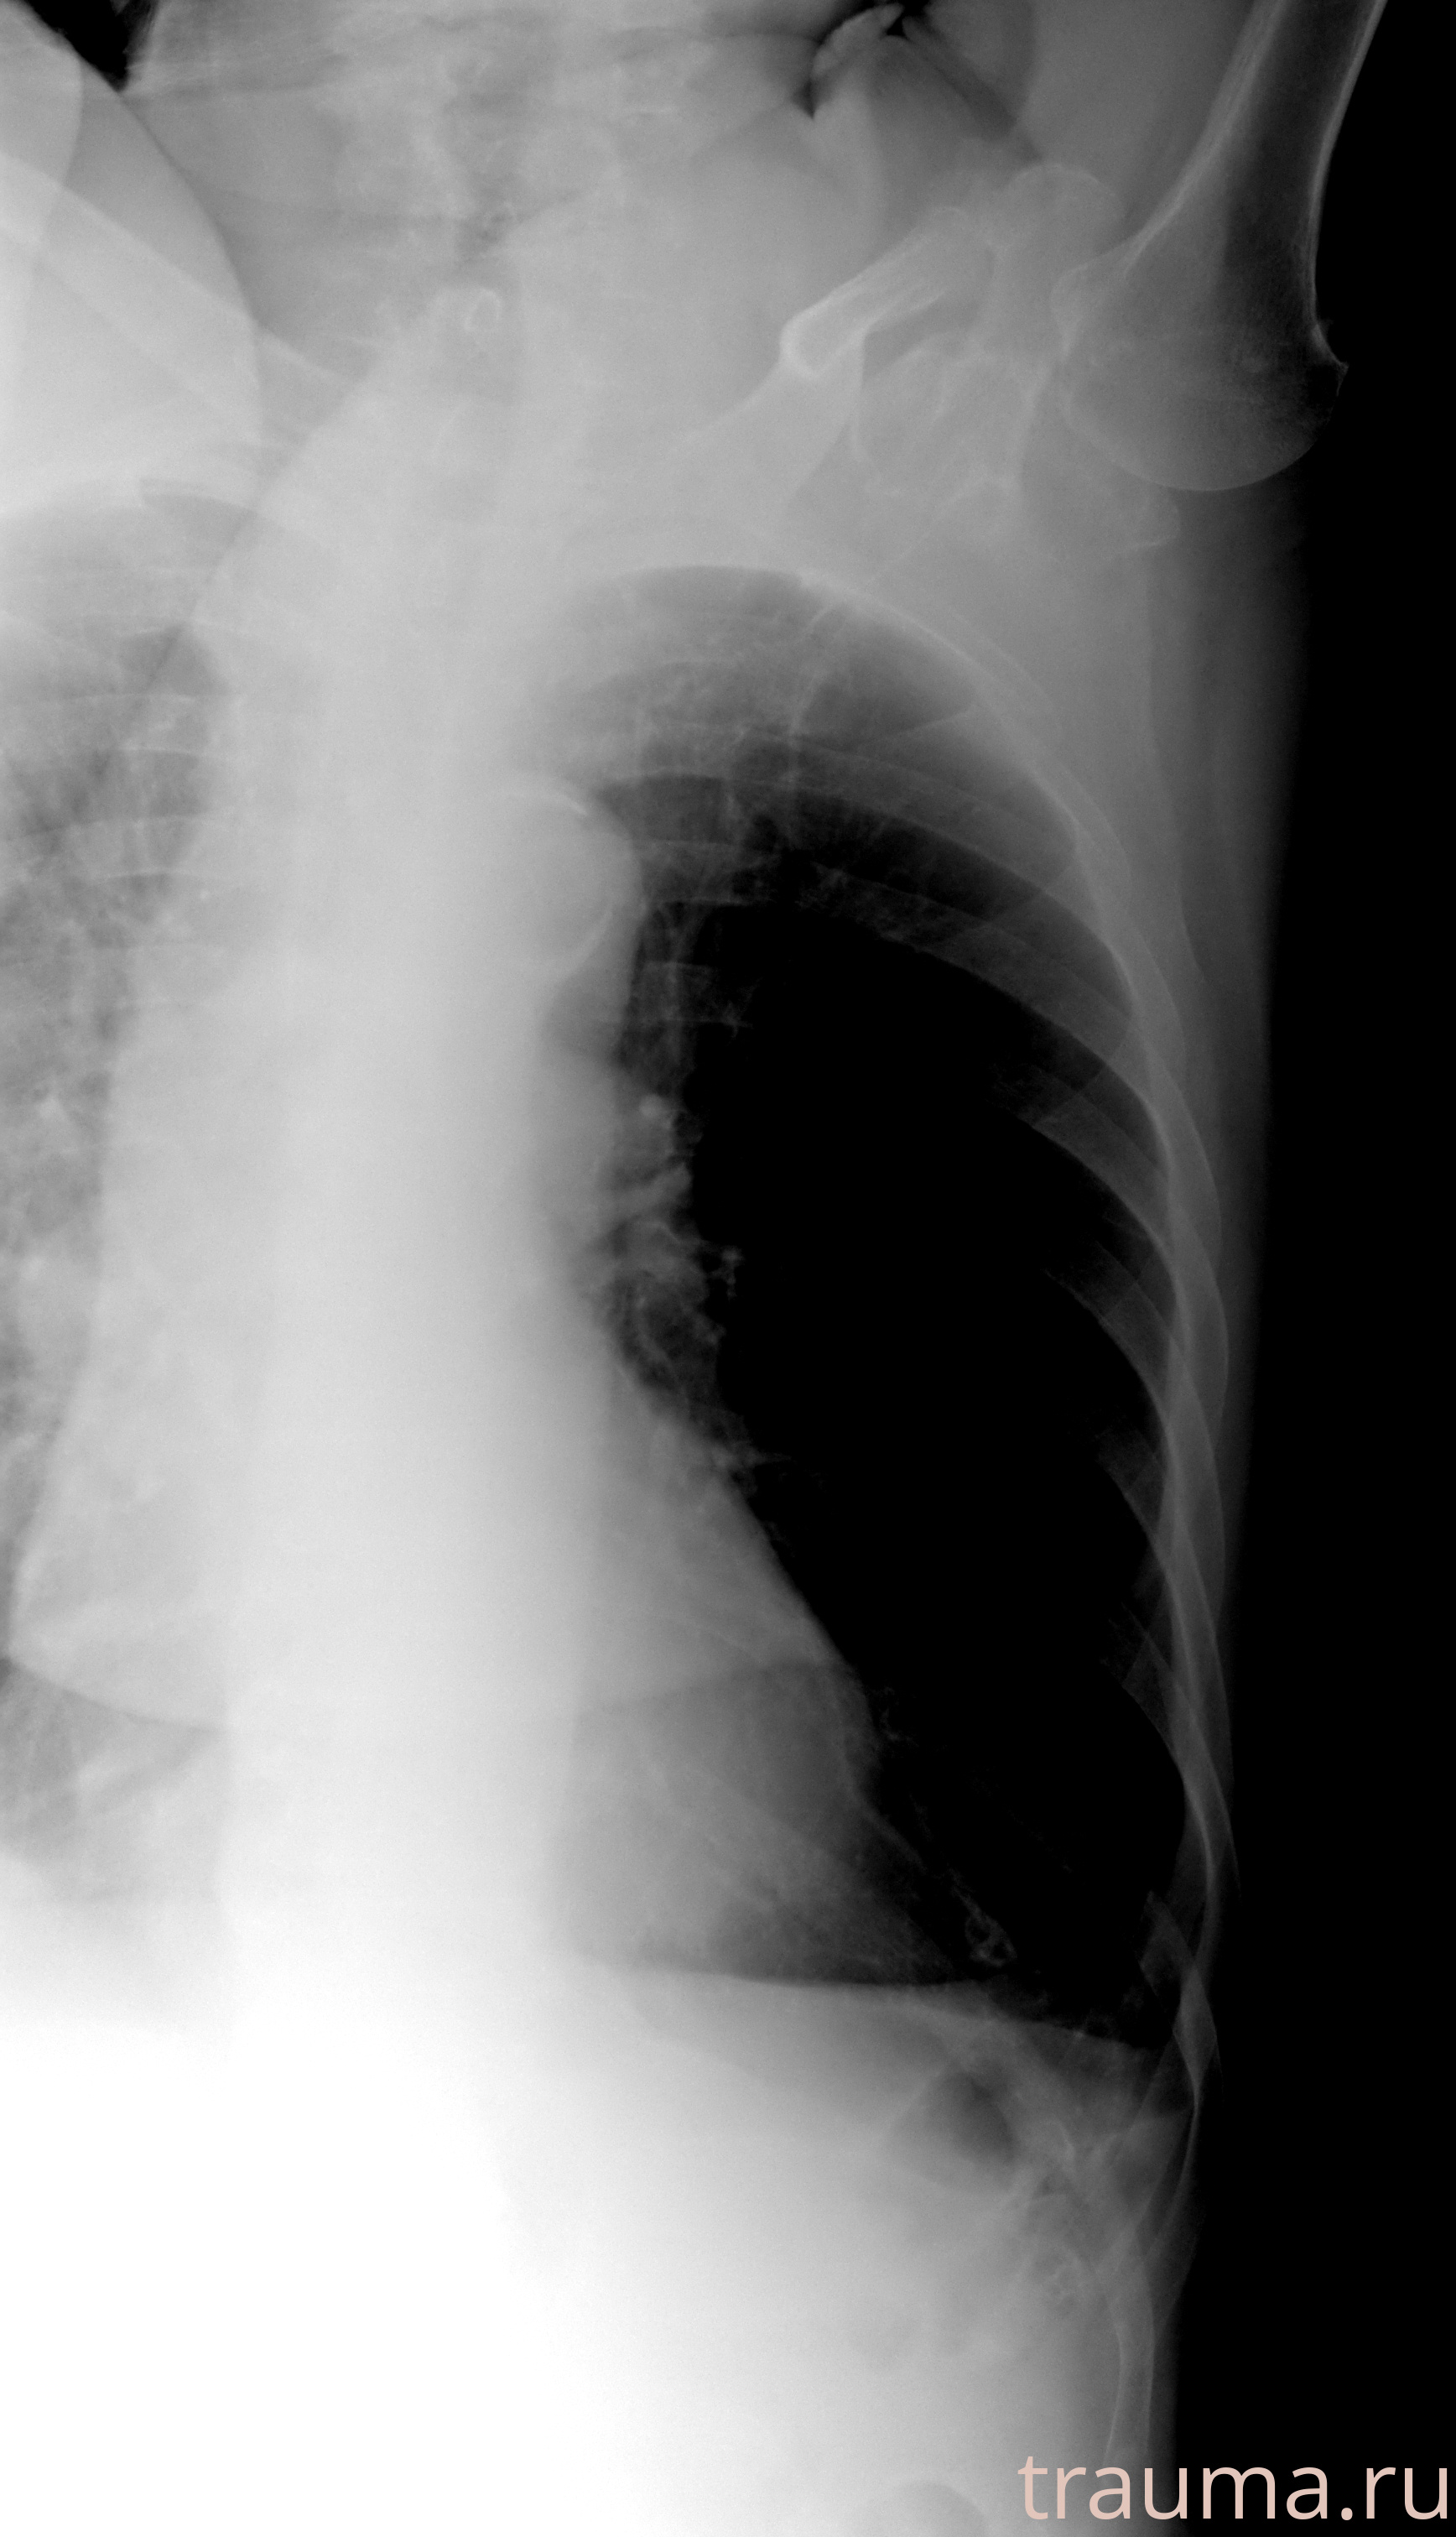

Рентгенограммы

Рентген на дому: по вашему адресу приезжает врач-рентгенолог, травматолог-ортопед с мобильным рентгеновским аппаратом, проводит диагностику травмы или заболевания, делает необходимые рентгенограммы, дает рекомендации по дальнейшему лечению. Получить качественные снимки в домашних условиях возможно благодаря уникальной методике, разработанной МосРентген Центром для института  Склифосовского

Яркость: 1   Контраст: 1   Инвертировать: 0 Увеличение: 1

Перетаскивайте мышь вверх/вниз для контраста, влево/право для яркости. Прокрутка колесом изменяет масштаб. Нажмите Сбросить для возврата к исходному изображению. При увеличении держите мышь в той области, которую хотите рассмотреть.